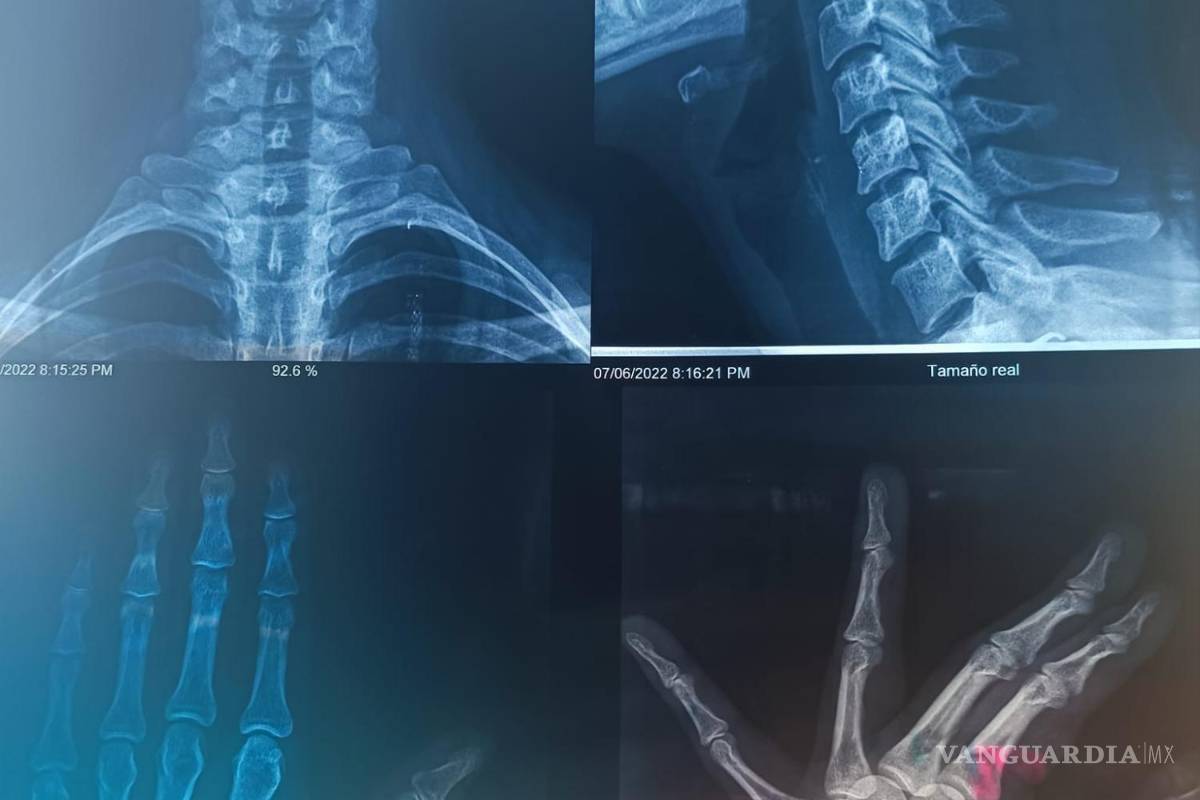

“Una prima mía y su esposo se subieron a mi coche y me comenzaron a golpear, dejándome diferentes lesiones que son las que se pueden ver en las fotos.

“La cosa llegó a tanto, que me golpearon en la nariz, cosa que hacía que yo batallara para respirar. Aparte que el esguince en el cuello me complicaba las cosas, hasta para comer”, expresó Alexa.

Con base al testimonio, declaró que la agredieron haciendo uso de cinturones y cadenas en las manos, lo que infligió más daño y causó lesiones severas que se vieron reflejadas durante la revisión médica de la víctima, además de esguinces en los dedos y torceduras en la nariz.

$!Imagenes de las radiografías de Alexa.